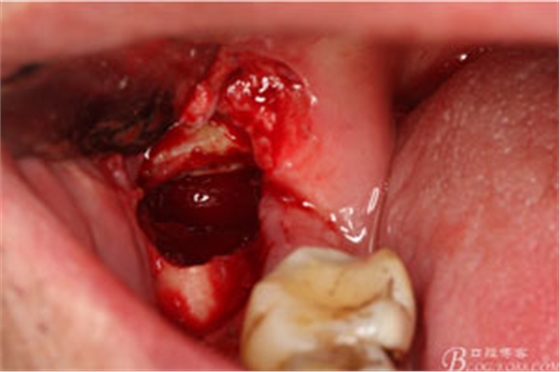

圖9.高速牙鉆分牙:

圖10.先頰舌向橫斷、然后再把牙冠近遠(yuǎn)中向縱分

圖11. “T”型的分牙。